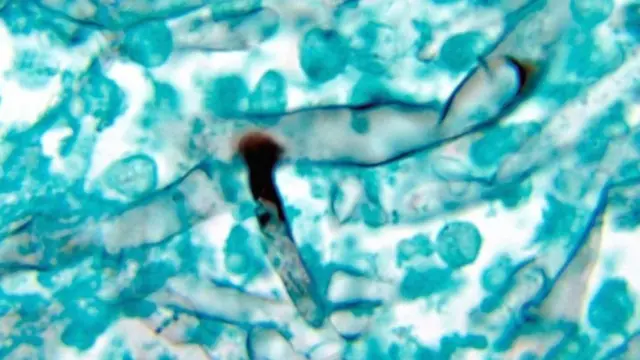

టైమ్స్ ఆఫ్ ఇండియా ప్రచురించిన ఒక కథనం ప్రకారం వైట్ ఫంగస్ను 'కాండిడియాసిస్' అంటారు. ఇది ఒక ఫంగల్ ఇన్ఫెక్షన్.

యూఎస్ సెంటర్ ఫర్ డిసీజ్ కంట్రోల్ అండ్ ప్రివెన్షన్ (సీడీసీ) వివరాల ప్రకారం ఈ వైట్ ఫంగస్ మెదడు, గుండె, రక్తం, ఎముకలు, శరీరంలోని మిగతా భాగాలపై ప్రభావం చూపిస్తుంది.

కాండిడా ఫంగస్ శరీరంలోనే పుడుతుంది

సీడీసీ వెబ్సైట్ ప్రకారం కాండిడియాసిస్ ఒక రకమైన ఫంగస్ వల్ల వస్తుంది. దానిని 'కాండిడా' అంటారు. కాండిడా ఫంగస్ శరీరంలోనే పుడుతుంది. ఇది నోట్లో, గొంతులో, శరీర స్రావాలకు సోకవచ్చు.